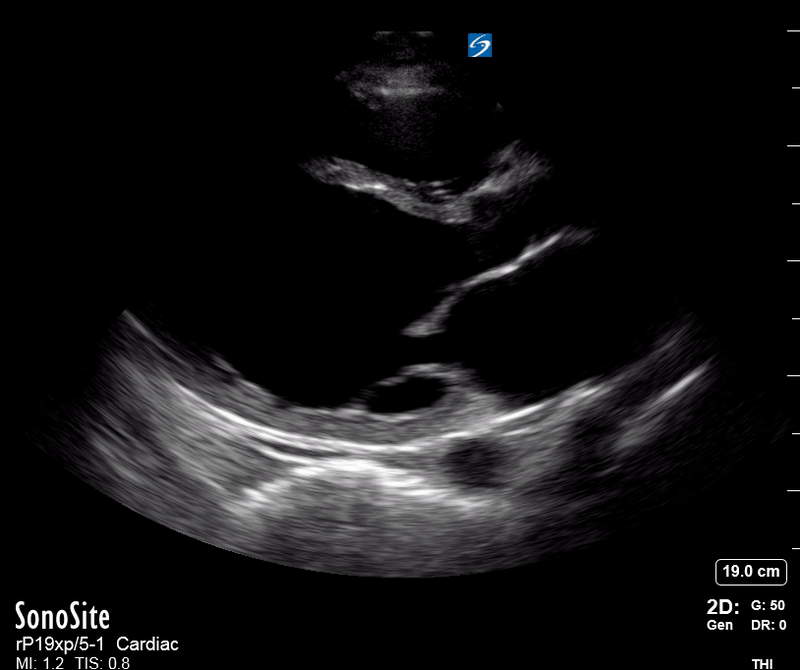

IVC exploration is best from the subxiphoid approach with longitudinal and transverse images. The IVC should be assessed in terms of overall size and collapsibility. The diameter is typically measured at its largest (end of expiration) at 1-2 cm distal to where the hepatic veins join the vena cava. An IVC diameter of ≥ 2 cm, especially with minimal or no collapsibility, is considered plethoric and correlates with increased RA pressure. An IVC of < 1 cm, particularly with complete collapse, is considered flat and indicates low preload and potential fluid responsiveness. An IVC diameter between 1 and 2 cm is typically normal.

PITFALLS

In a long-axis view, beware of not sliding off the centre of the vessel, as this will underestimate the size of the IVC and overestimate its collapse. Obtaining long and short axis views may help avoid this pitfall. Another mistake is confusing the descending aorta for the IVC, particularly when scanning in long-axis. Although the IVC may appear to pulsate, the aorta has a thicker wall, and its position is to the patient’s left. Following the IVC upwards will reveal the hepatic veins junction and the entrance to the RA, while the aorta will travel behind the heart. The IVC moves both anterolaterally and craniocaudally with inspiration, and this should be considered during visualization or measuring. For this very reason, measuring in M-mode is not recommended as it would not be accurate.

In a shocked patient, a flat or highly collapsible IVC correlates well with low preload estates (hypovolaemia, haemorrhage, sepsis). Yet by itself, a small IVC is not enough to define low preload and could also represent a normal finding.

Conversely, a distended, not collapsing IVC suggests distal obstruction in a shocked patient. Potential causes include LV failure, massive PE, tension pneumothorax and cardiac tamponade. Nonetheless, there are other causes of elevated cava / RA pressure, such as chronic pulmonary hypertension.